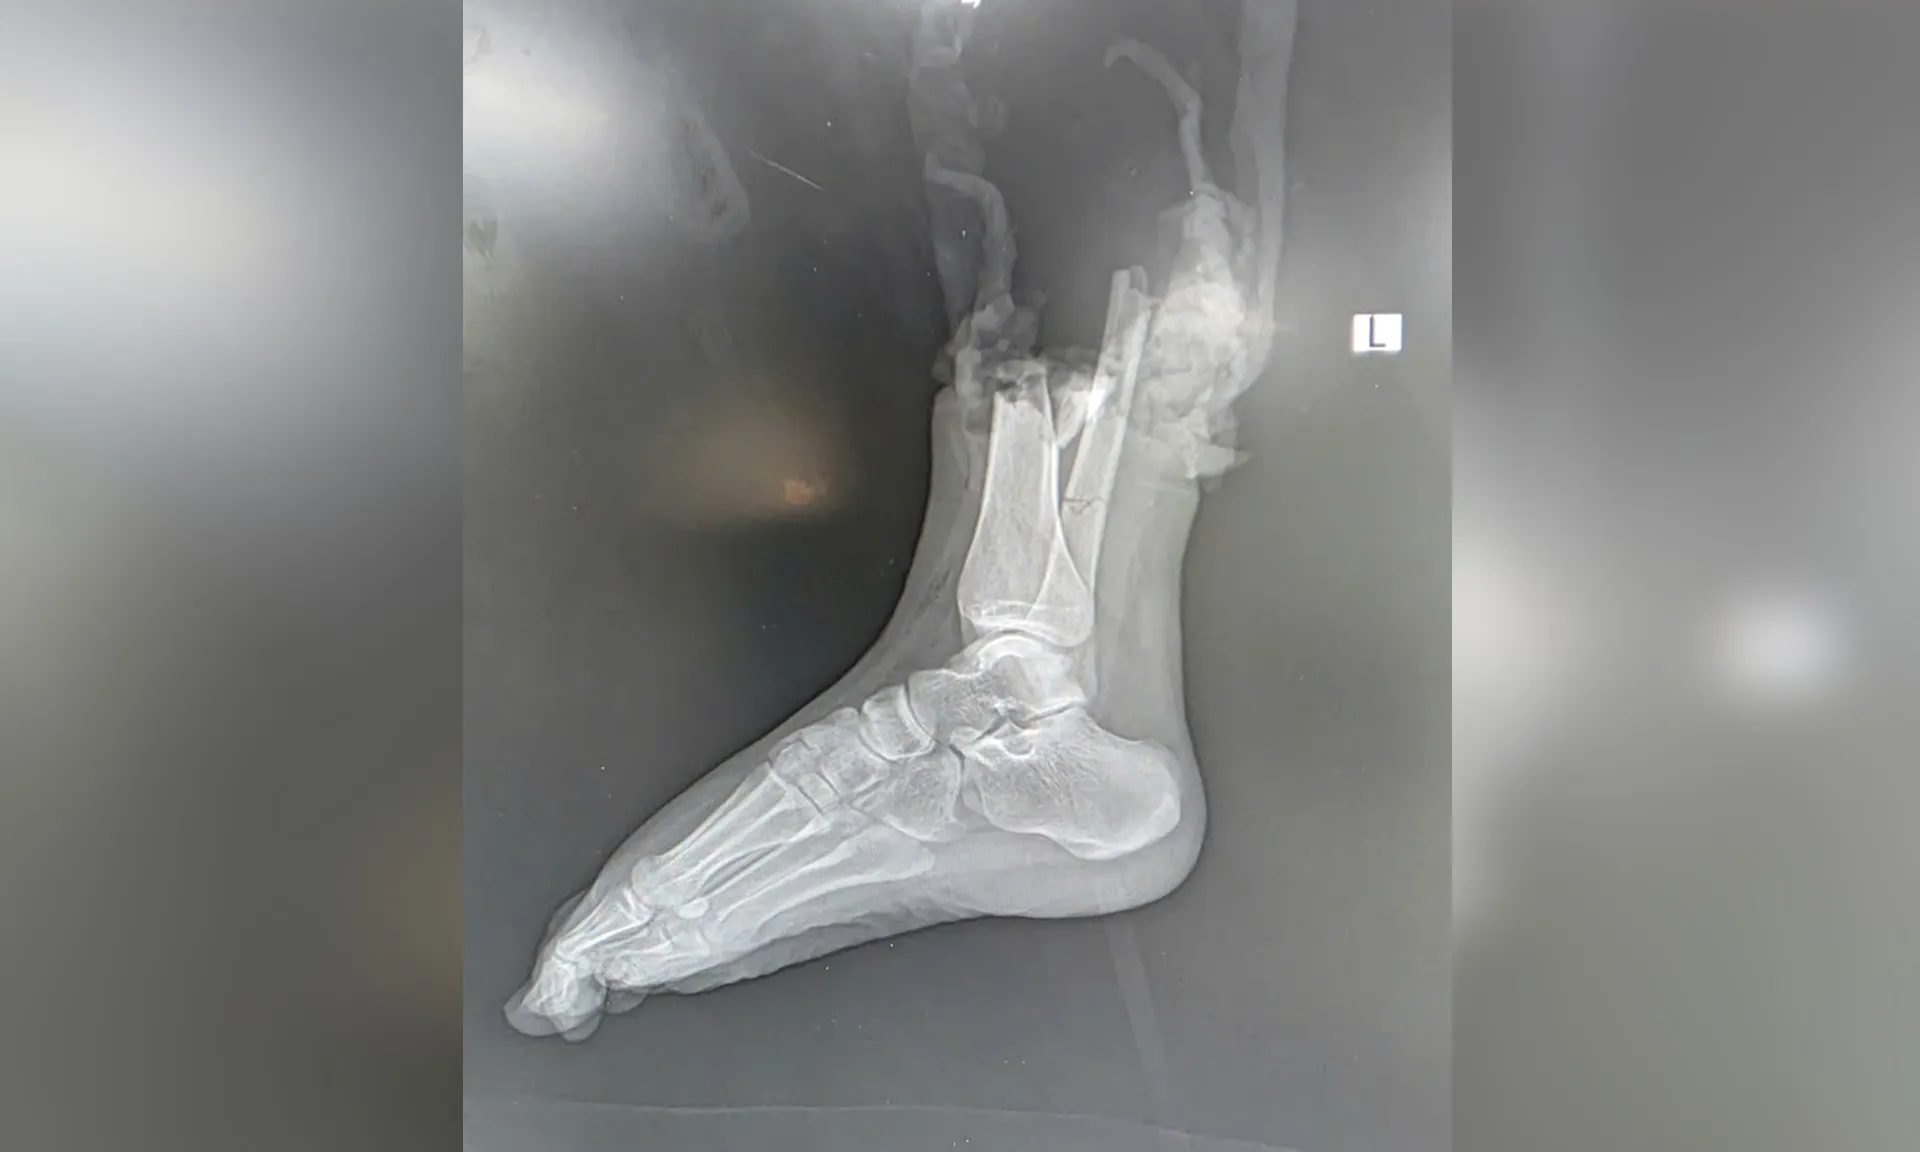

Sau cú va chạm mạnh giữa mô tô phân khối lớn và xe máy, nữ sinh Đ.P. (19 tuổi, quê Bắc Ninh) - người điều khiển xe máy bị đứt lìa ở vị trí phức tạp - 1/3 dưới cẳng chân phải, kèm dập nát phần mềm.

Sau hơn 6 giờ phẫu thuật căng thẳng, phần chi thể đứt rời được trồng nối thành công. Sau phẫu thuật gần 2 tuần, bệnh nhân đã khỏe mạnh và có thể cử động được các ngón chân, cho thấy kết quả phục hồi khả quan.